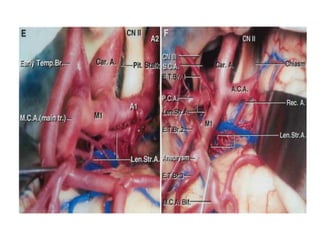

Branching pattern M1

Early branches

• Cortical Branches from main trunk

proximal to MCA division

• types

• early temporal branches- more

common

• early frontal branches

Early branches • CorticalBranches from main trunk proximal to MCA division • types • early temporal branches- more common • early frontal branches

Perforating branches

• Lenticulostraite arteries - branches of MCA that

enter anterior perforating substance (APS)

• origin from superior or posterosuperior MCA

• 3 groups : medial, intermediate and lateral

• MEDIAL: least constant, 1-5 branches from M1, enter

medial APS

• INTERMEDIATE: constant, few branches dividing,

atleast 1 major artery

• LATERAL: constant S shaped course, enter

posterolateral part of APS

Perforating branches • Lenticulostraitearteries - branches of MCA that enter anterior perforating substance (APS) • origin from superior or posterosuperior MCA • 3 groups : medial, intermediate and lateral • MEDIAL: least constant, 1-5 branches from M1, enter medial APS • INTERMEDIATE: constant, few branches dividing, atleast 1 major artery • LATERAL: constant S shaped course, enter posterolateral part of APS

Editor's Notes

• #4 at the medial end of the sylvian fissure, lateral to the optic chiasm, below the anterior perforated substance, and posterior to the division of the olfactory tract into the medial and lateral olfactory striae